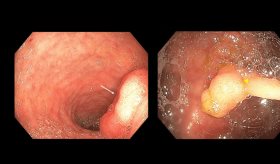

Los pólipos hamartomatosos solitarios son típicamente benignos y se descubren con mayor frecuencia en la población pediátrica, son muy raros en personas adultas.